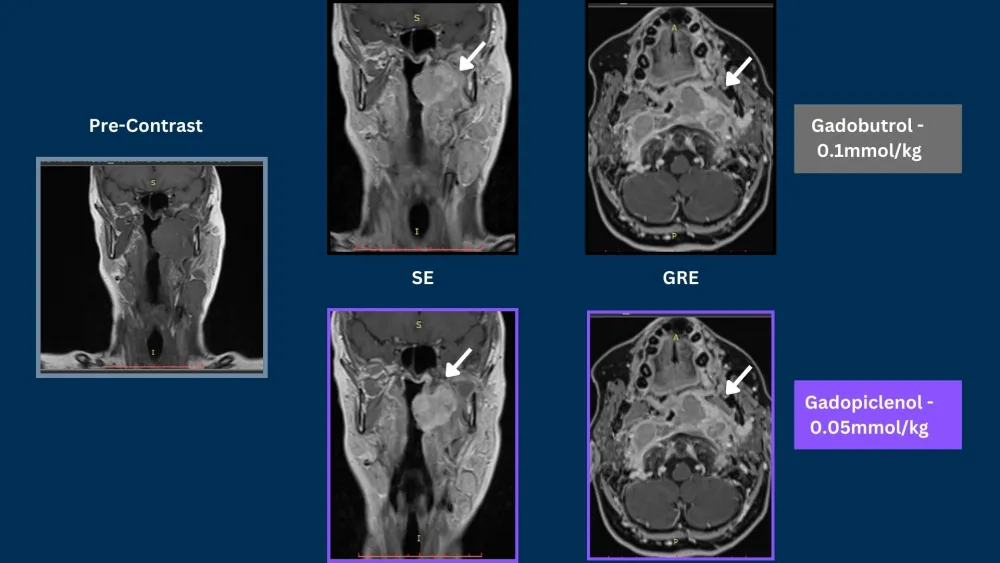

Phase III clinical trials, in CNS and Body, demonstrated that gadopiclenol at a dose of 0.05 mmol/kg was noninferior to gadobutrol at a dose of 0.1 mmol/kg in terms of lesion visualization.5,6

Case 366 year old female2

Pharyngeal Cancer

SE = Spin Echo, GRE = Gradient Echo, 3DGRE = 3D Gradient Echo, TSE = Turbo Spin Echo

Phase III PROMISE trial in the body demonstrated that gadopiclenol at a dose of 0.05 mmol/kg was noninferior to gadobutrol at a dose of 0.1 mmol/kg in terms of lesion visualization.6